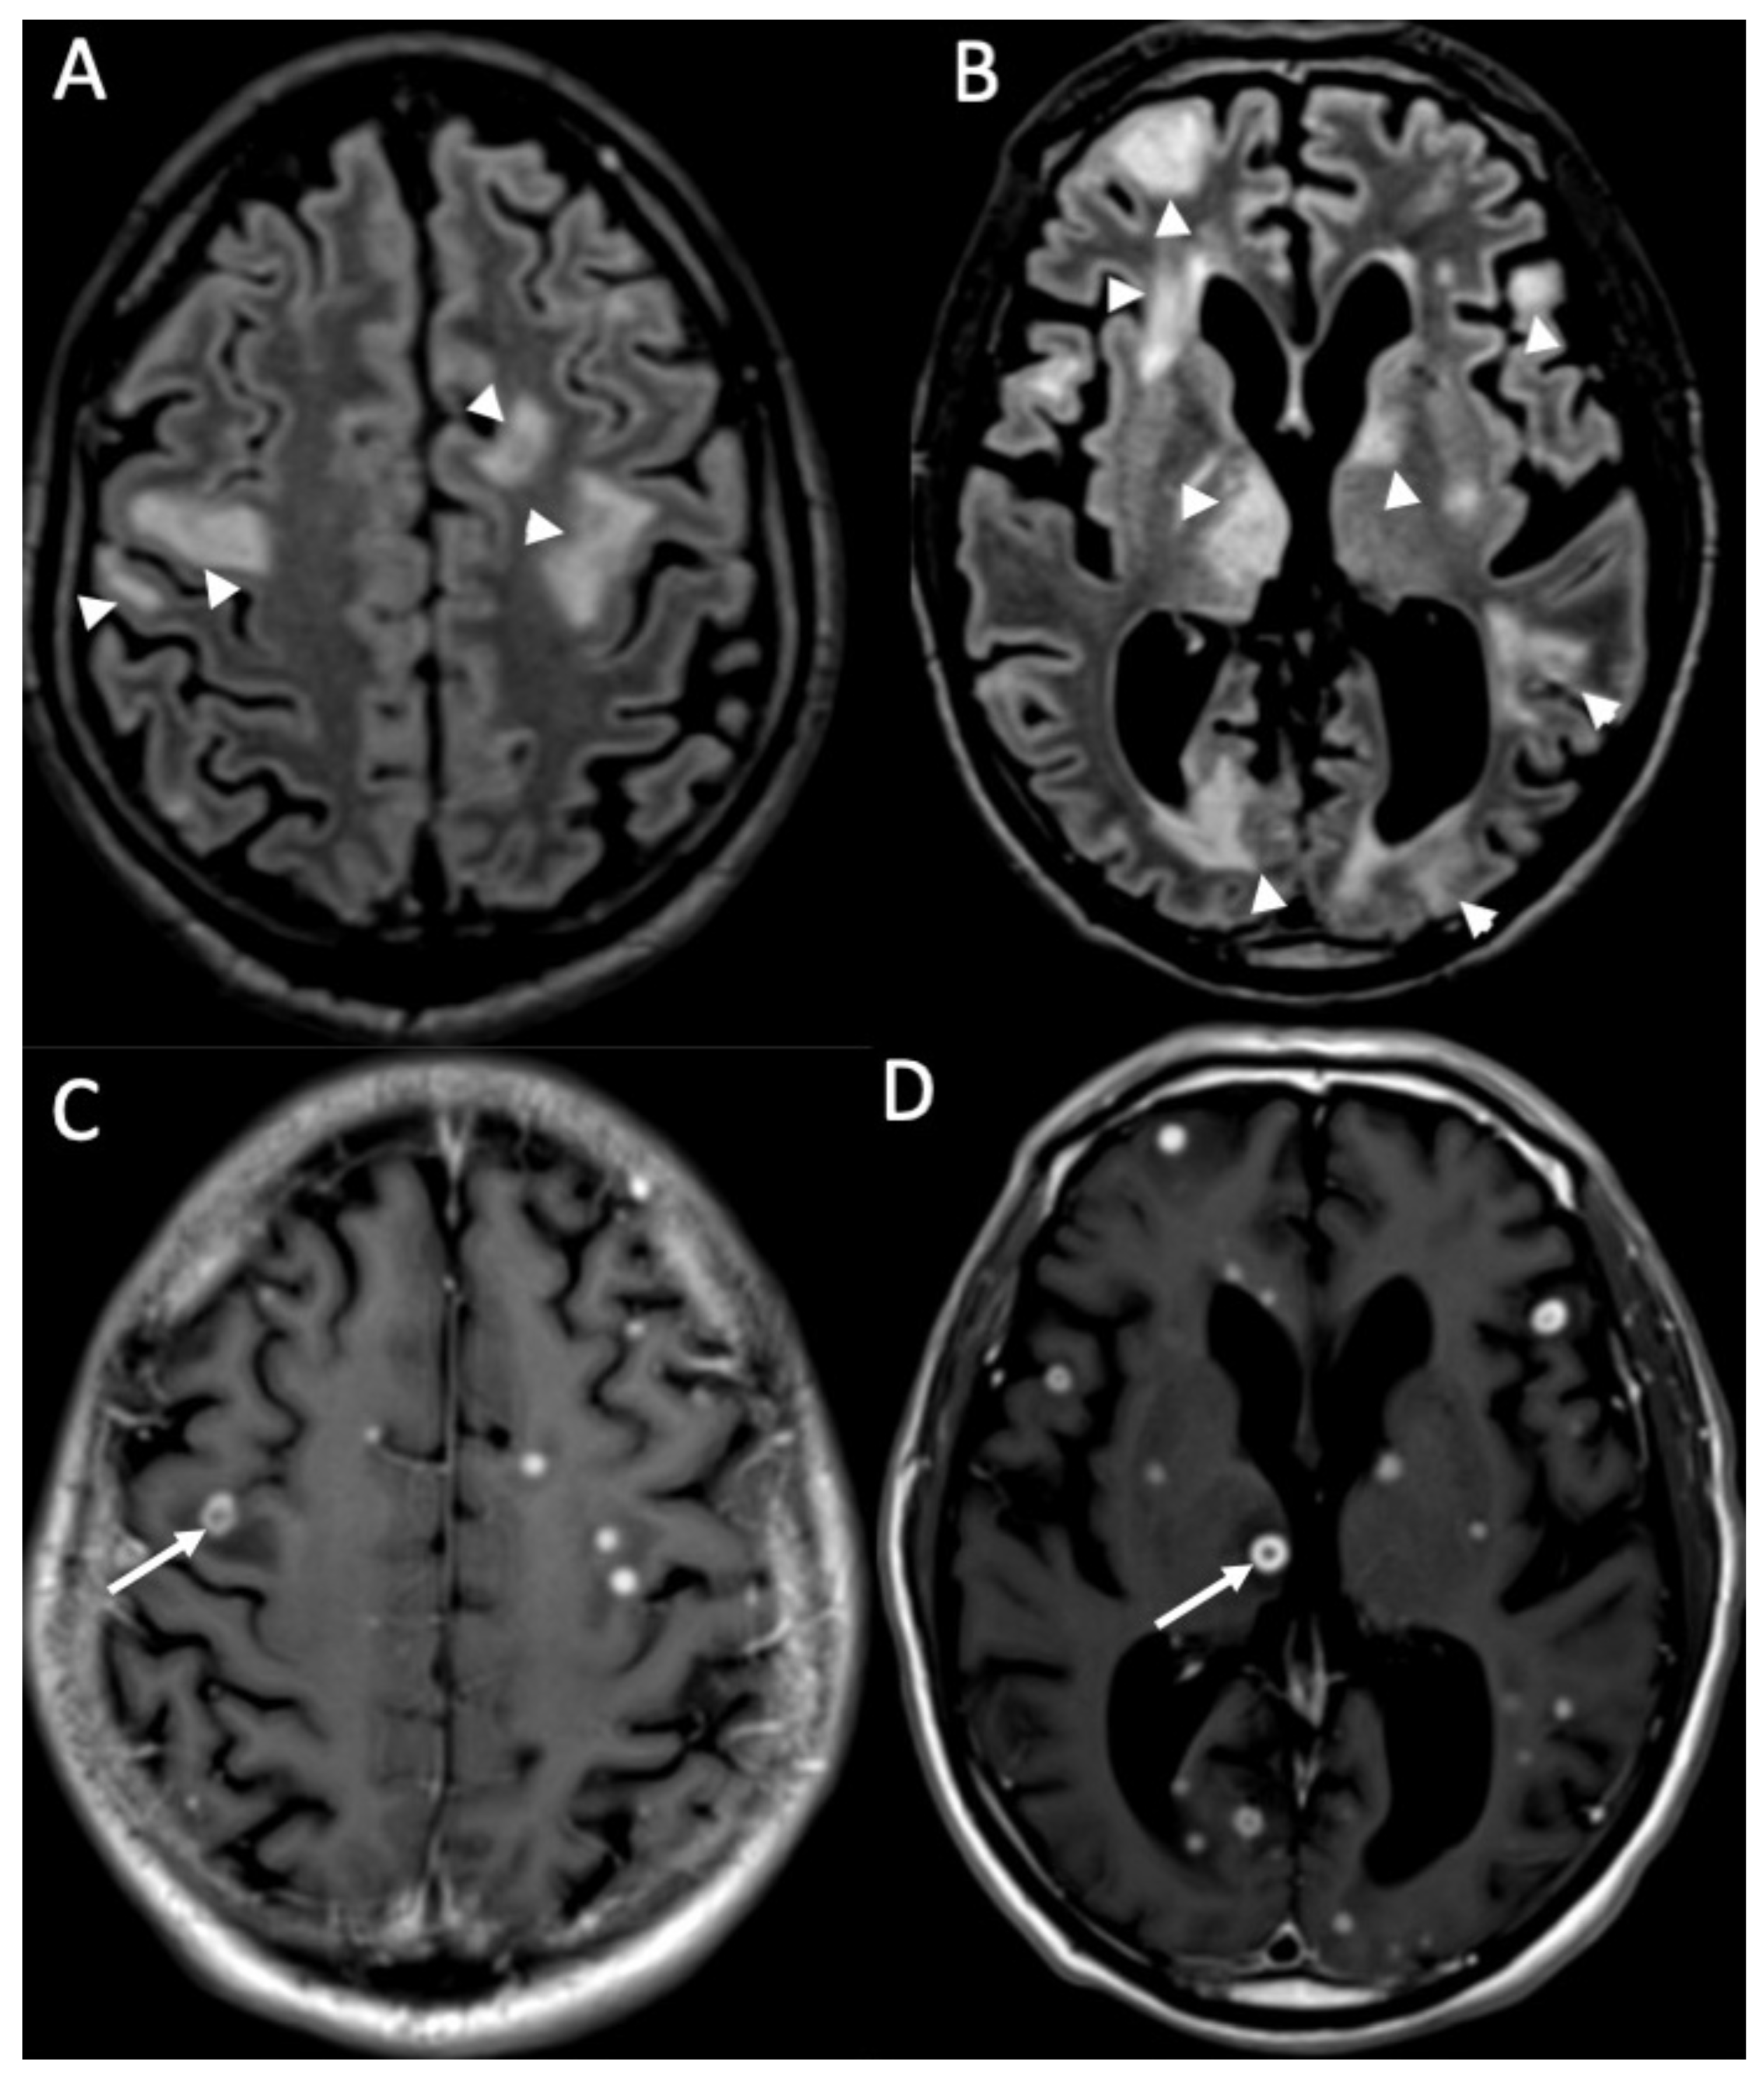

| Candida albicans | • Microabscesses • Vascular lesions |

| Aspergillus fumigatus | • Abscesses • Vascular lesions |

- Mathur, M.; Johnson, C.E.; Sze, G. Fungal Infections of the Central Nervous System. Neuroimaging Clin. N. Am. 2012, 22, 609–632. [Google Scholar] [CrossRef]

- Palacios, E.; Rojas, R.; Rodulfa, J.; González-Toledo, E. Magnetic Resonance Imaging in Fungal Infections of the Brain. Top. Magn. Reson. Imaging 2014, 23, 199–212. [Google Scholar] [CrossRef] [PubMed]